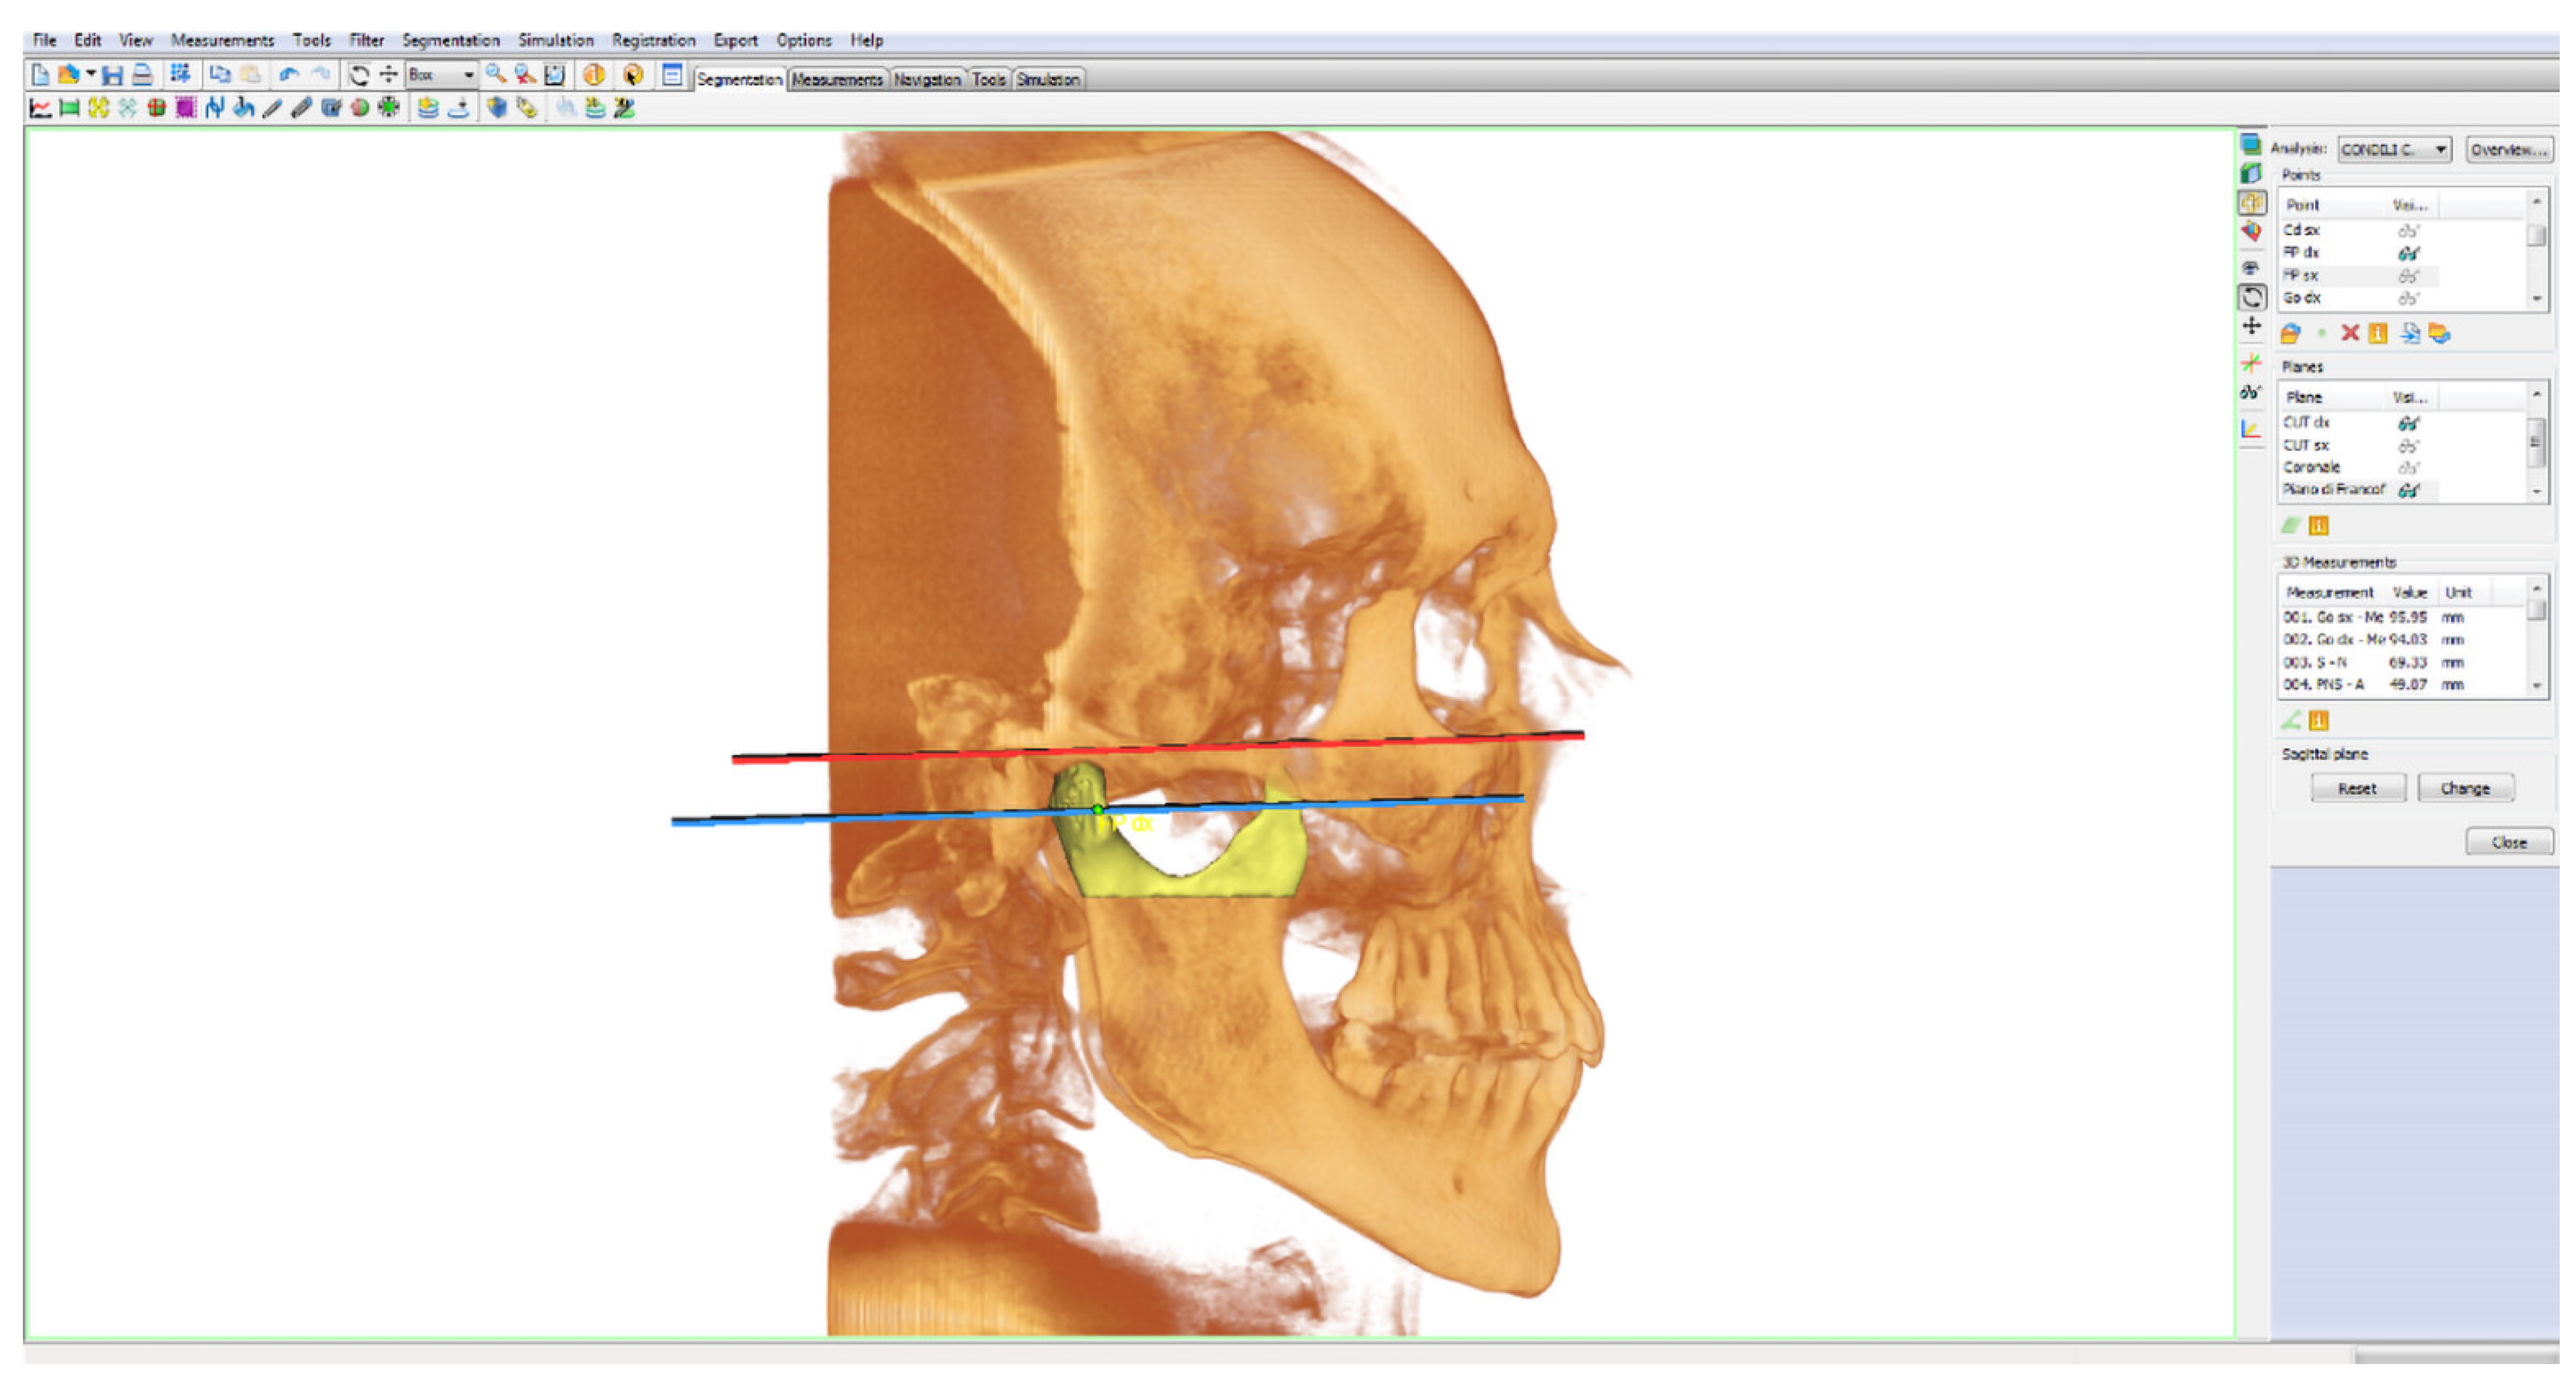

- Frankfurt plane: calculated as the plane passing through the lower right and left orbital points (right/left OR) and from the right and left porion points (right/left Po);

- Cut plane of the right condyle (right CUT): plane passing through right FP and parallel to the Frankfurt plane;

- Cut plane of the left condyle (left CUT): plane passing through left FP and parallel to the Frankfurt plane.